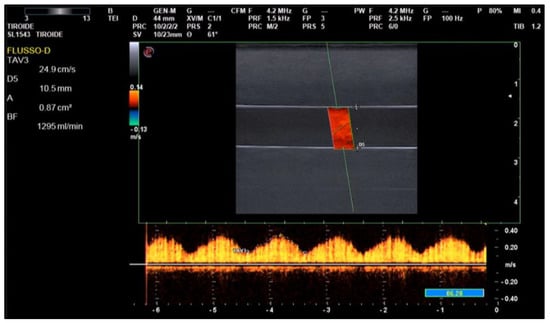

Figure 8 shows a screenshot of an echo-doppler measurement.

Figure 8. The echo-doppler flow measurement performed on the phantom.